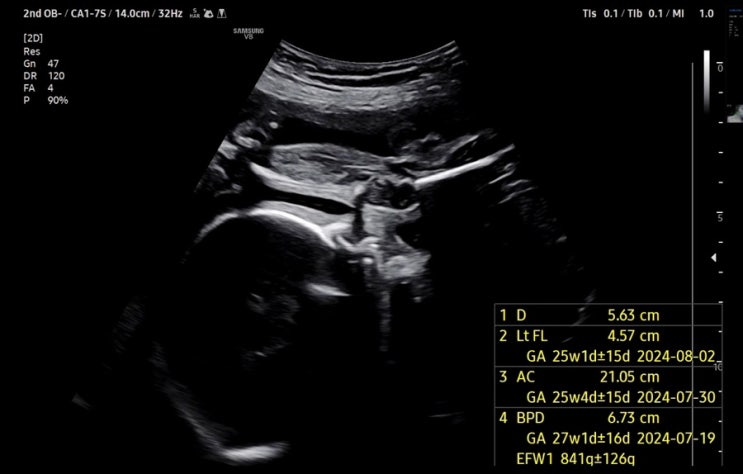

임신일기 6 / 5주~37주 아기 초음파 사진, 꼬물꼬물 태동

임신일기 6 ??용용이 초음파 사진들 ??용용이가 움직인다, 태동 #초음파사진 처음으로 용용이 ...